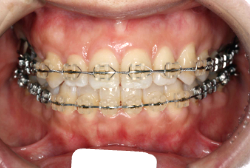

「歯並びの凸凹を直したい」という主訴で来院したケースです。診断の結果、たしかに「叢生」という隙間が足りないと言うことが原因の凸凹症例でした。

しかし、それ以上に問題なのは「前歯の噛み合い方が深すぎる」という症状で、初診の歯の正面写真を見ると下の前歯が全く見えません。こういう症状を矯正学では「過蓋咬合(かがいこうごう)」と言います。過蓋咬合を放置すると、将来的に顎関節に悪影響を与えるとされており、顎関節症の原因因子の一つです。また下の前歯の先端が、上の前歯の裏側の歯茎と強く接触するため、歯周病の原因にもなります。

検査の結果、凸凹が軽症なため非抜歯で矯正すること可能と判断、マルチブラケット装置にて治療しました。治療後は歯並びが綺麗になっただけでなく、噛み合わせ的にも正しい状態が確立しています。